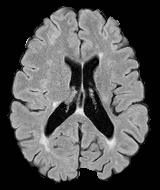

Patch size is another important parameter of the network. In computer vision applications such as object detection, usually a whole 2D image is used as a feature. However, full 3D medical images can not typically be used because of memory limitations. Fig. 4 shows examples of lesion memberships obtained with different sized 2D patches. As the patch sizes increases, the false positives that are mostly observed in the cortex tend to decrease. Fig. 5 shows a plot of Dice and LFPR with various patch sizes, ordered from left to right according to their increasing size. Note that smaller patches ( to ) produced significantly lower Dice and higher LFPR compared to other patches (), as seen from the memberships in Fig. 4. Also some of the highest Dice and lowest LFPR were observed for patches with large in-plane size, i.e., , , and . It was observed in Fig. 5 that there is no significant difference between Dice coefficients for , , or , but LFPR of both and are significantly lower than that of (). We chose as the optimal patch size. Other choices of smaller and patches (not shown) yielded worse results. Note that although training was performed with different patch sizes, the memberships were generated slice by slice, as the trained model consisted only of convolutions and did not need any information about patch sizes.

In our experiments, we used large 2D patches similar to Ghafoorian et al. (2017b), in comparison to isotropic 3D patches as used before, e.g., in Valverde et al. (2017), in Wachinger et al. (2017), and in Kamnitsas et al. (2017). The rationale behind using large anisotropic patches is twofold. First, experiments with full 3D isotropic or patches showed little or no improvement in Dice and led to increased false positives, with memberships similar to the one with patches, as shown in Fig. 4. Larger isotropic patches, e.g. or , showed inferior segmentation, and in some cases, optimization did not converge. The reason is that the FLAIR images in the test datasets had inherently low resolution in the inferior-superior direction, mm and mm compared to in-plane resolution of mm. Therefore 2D axial patches capture the high resolution in-plane information that represents the original thick axial slices. Second, the lesions are usually focal and small in size, unlike other brain structures. Therefore a very large isotropic patch around a small lesion can include superfluous information about the lesion, which can increase the amount of false positives. Note that with in more recent studies employing high resolution 3D FLAIR sequences, it is trivial to extend the algorithm to accommodate for 3D patches.